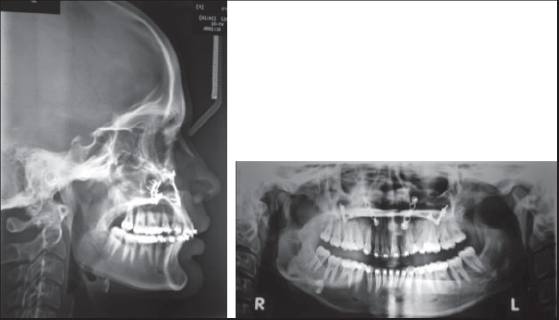

a. The skeletal stability for both Group I [Figures 35] and Group II [Figures 68] was measured at three different periods; preoperative (T1), 1-week postoperative(T2), and 6-month postoperative (T3) using a lateral cephalogram and analyzed using cephalometric analysis. The cephalometric analysis was carried out considering the following points[4] [Figure 9].

thumb

Figure 6: Preoperative lateral cephalogram and orthopantamogram-Group II

Figure 7: 1-week postoperative lateral cephalogram and orthopantamogram- Group II

Figure 8: 6-month postoperative lateral cephalogram and orthopantamogram- Group II